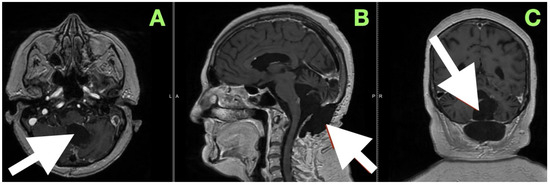

Background and Clinical Significance: Fourth ventricular epidermoid cysts are among the least frequently encountered intracranial tumors (less than 1%). Their slow growth pattern along cisternal and subarachnoid spaces, and their close proximity to neurovascular structures (brainstem–cerebellar), create difficulty for surgical treatment. Total removal is often complicated by the capsule’s adherence to eloquent structures and requires a thoughtful surgical approach of weighing radical resection versus neurologic/function preservation. This case description provides an example of using careful clinical–radiological correlation and anatomy-dissecting microsurgery as a method of permanent decompression and neurologic recovery with low operative risk. Case Presentation: A 57-year-old female presented with impaired stability of gait, gaze-evoked nystagmus, appendicular ataxia, minimal ipsilateral hypotonia, and mild bulbar dyscoordination. Imaging (MRI, MRA) revealed a large, lobulated mass that was lobulated and avascular centered in the left cerebellar hemisphere, with an extension into the vermis and cisterna magna, and partial filling of the fourth ventricle with classic epidermoid imaging. Resection was performed via a midline suboccipital telovelar approach with microsurgery, relying on native arachnoid planes and quadrant opportunities of decompression, while preserving critical neurovascular structures. A thin rim of capsule intimately adherent to the floor of the ventricle was intentionally left to minimize irreversible cranial nerve injury. Histology showed keratinizing stratified squamous epithelium with laminated keratin and cholesterol clefts. Following resection, truncal stability, limb coordination, and ocular pursuit improved without additional deficits. Initial and 3-month postoperative MRI showed total decompression, re-established CSF pathways, and no recurrence. Conclusions: This case demonstrates that maximal safe resection (with function preservation) through natural anatomy corridors can achieve excellent neurologic results in fourth ventricular epidermoids. Lifelong MRI surveillance will be needed due to the srisk of delayed recurrence even after near-total resection. Full article

Figure 1